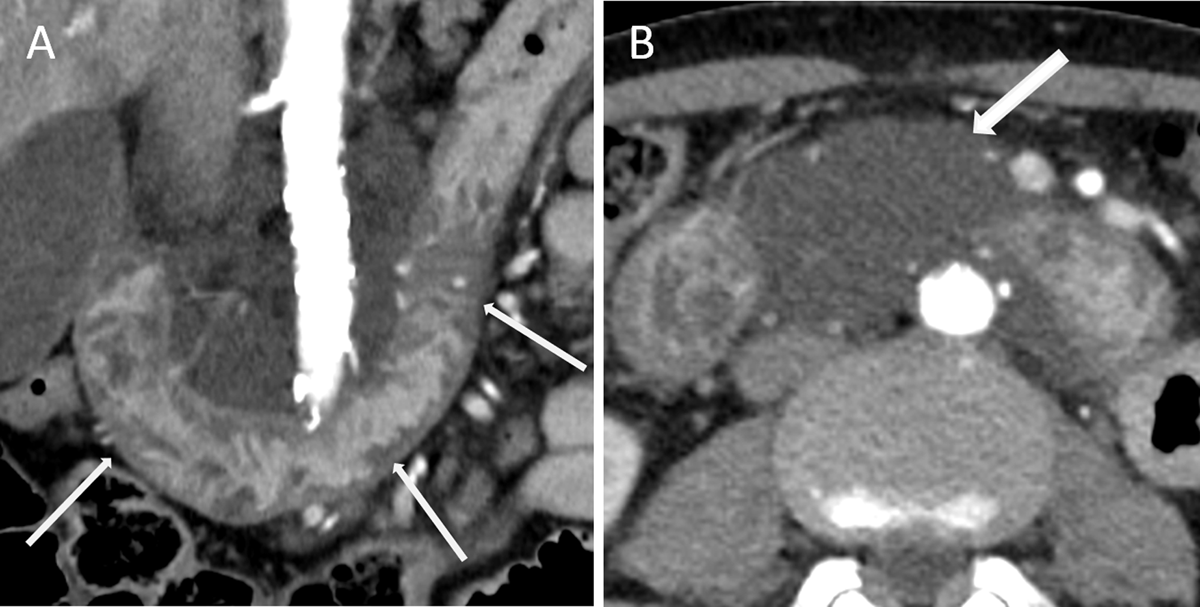

Eight years later, a repeat CT showed extension of the low-attenuation thickening to the whole duodenum (Figure 2A, arrows), and a 10-centimeter mesenteric cystic mass extending to the liver hilum without tissue infiltration (Figure 2B, arrow).

Figure 2

The radiological features and its localization highly suggested the diagnosis of cystic lymphangioma. Final diagnosis was primary intestinal lymphangiectasia, also known as Waldmann’s disease.